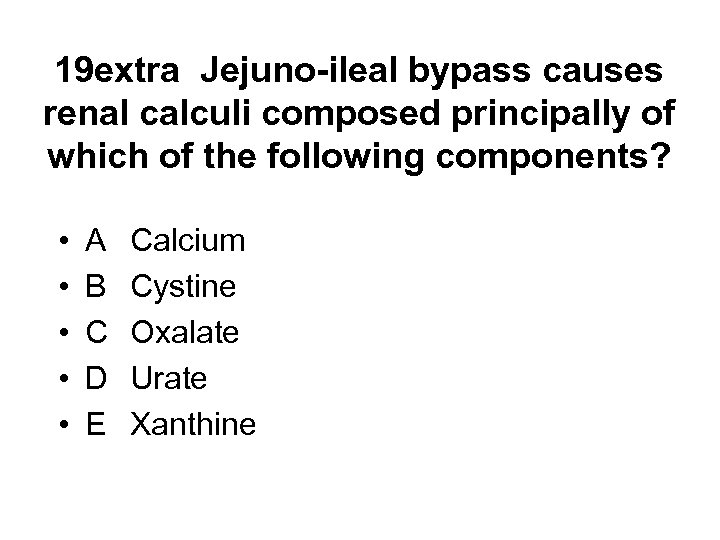

20. Which of the following infections is not associated with glomerulonephritis? • • • A B C D E Plasmodium malaria HIV 1 Hantavirus Schistosoma mansoni Mycobacterium leprae

20. Which of the following infections is not associated with glomerulonephritis? • • • A B C D E Plasmodium malaria HIV 1 Hantavirus Schistosoma mansoni Mycobacterium leprae